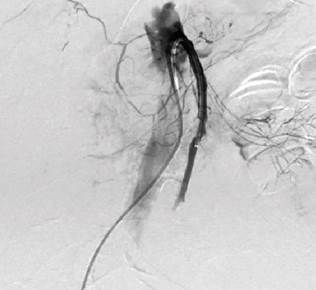

The patient was immediately taken for an abdominal aortography, selective arteriography of the abdominal vessels, and thromboembolectomy by interventional radiology, finding occlusion of the common hepatic, superior mesenteric, and inferior mesenteric arteries (Figure 2). Using 6 Fr and 8 Fr indigo catheters, aspiration thrombectomy was performed on multiple occasions, and acute and subacute clots were obtained, with which it was only possible to revascularize the proximal third of this artery with outflow through the pancreatoduodenal arch that reperfused the hepatic artery proper and the first jejunal branch (Figure 3). The distal two-thirds of the superior mesenteric artery could not be revascularized due to poor outflow. Immediately after the procedure, the patient was taken to ERCP. In the second duodenal portion, marked edema that did not allow visualization of the papilla was observed, so the procedure was suspended.

Source: Authors’ archive.

Figure 3 Reperfusion of the hepatic artery proper and first jejunal branch.